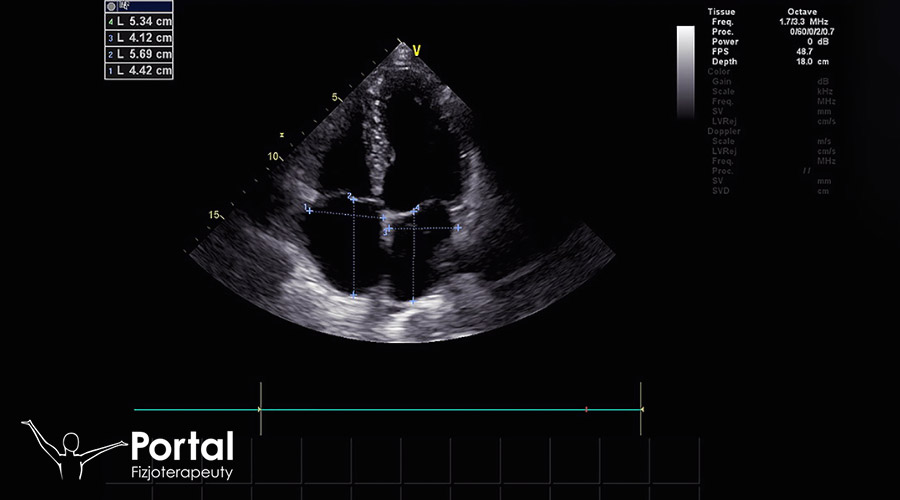

Badanie echokardiograficzne (echokardiografia, ECHO) ocenia strukturę oraz czynność mechaniczną serca za pomocą ultradźwięków. Podczas badania wykorzystuje się zjawisko odbicia fal